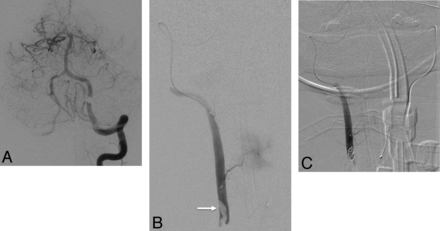

In the setting of a severe vascular injury, such as vertebral artery fistula or frank extravasation, proximal occlusion of the vertebral artery alone is insufficient treatment because the lesion will continue to derive flow from the patent distal cervical vertebral artery in retrograde fashion. Occlusion both proximal and distal to the lesion must be secured in such cases. In many instances, it is possible to advance a catheter or microcatheter beyond the level of the lesion in antegrade fashion to perform an initial distal occlusion. Proceeding in retrograde fashion, one can use coils, glue, particles, or balloons to occlude the vertebral artery at and below the level of the pathology.17 In the case of a fistula or frank extravasation, embolic materials may also be placed outside the arterial lumen, as long as sufficient care is taken to avoid venous migration. When the proximal segment of the affected vertebral artery is already completely or near-completely occluded, coils can be placed distal to the level of injury by navigating a microcatheter through the contralateral vertebral artery, across the vertebrobasilar junction, and retrograde to the level of vascular injury (Fig 3).18

A 45-year-old man with fracture and diastasis of the right C4–C5 facet joint, with fracture extending through the right C5 transverse foramen, following a motorcycle collision. A, Anteropostior DSA of the left VA shows retrograde flow down the distal right VA due to proximal occlusion. B, A microcatheter was passed from the left VA to the vertebrobasilar junction, and retrograde microcatheterization of the right VA was performed. Hand-injection DSA demonstrates thrombus (arrow) in the lumen. C, Anteroposterior DSA with injection of the microcatheter following placement of coils above the thrombus to prevent embolization.

Regardless of the level or degree of vertebral artery pathology, the technique of occlusion must be designed to maintain the patency of the PICA origin and the vertebral artery contribution to the anterior spinal artery on the treatment side. Reconstruction of the injured segment should always be considered before vertebral artery occlusion, especially when the injured vessel is markedly dominant. However, neurologic sequelae from unilateral vertebral artery occlusion are unlikely in the presence of a normal contralateral vessel and in the absence of angiographic demonstration of branches to the spinal cord.19